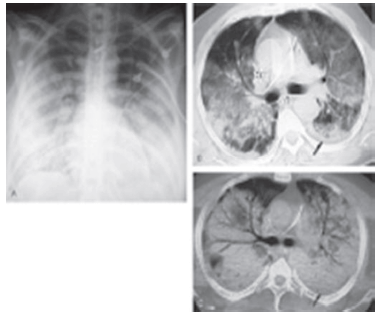

Um paciente de 48 anos foi admitido na UTI com história de uma forte gripe até uma semana atrás. Apresentava síndrome febril, tosse, dispnéia; há uma hora, apresentou hipotensão arterial. Baseado na história e na imagem, podemos afirmar o diagnóstico de:

Provas